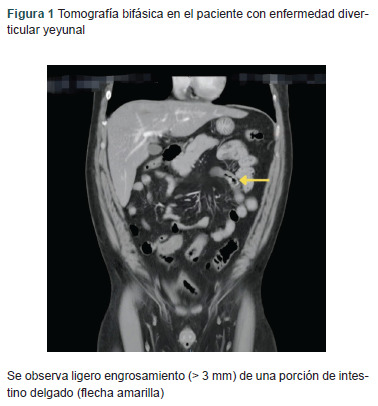

Clinical case: A 48-year-old male patient presented with massive digestive bleeding of unknown origin, initially treated with angiography and embolization, with a satisfactory outcome. However, six days after discharge, the patient experienced new massive bleeding that required an urgent exploratory laparotomy, during which jejunal diverticular disease (JDD) of the small intestine was identified.